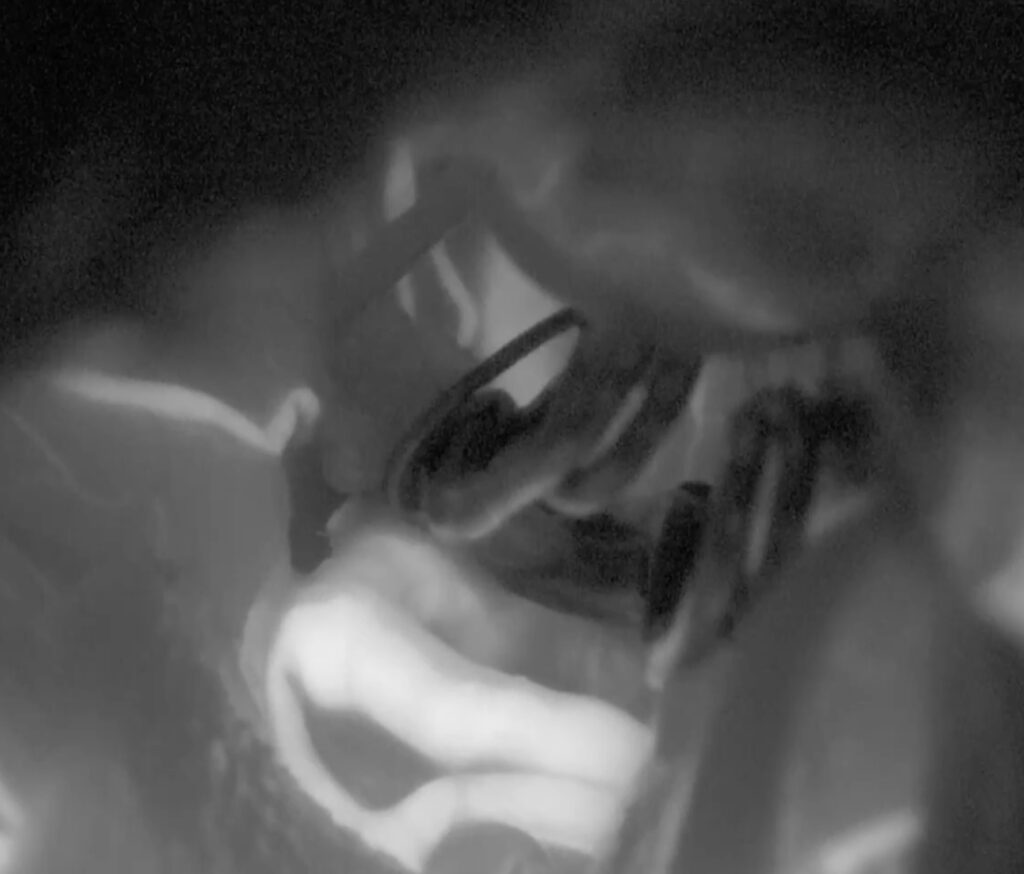

ICGやドップラーで確認し、閉創です。オーブアイは色調や焦点深度がフットスイッチで自在に変えられるのが利点です。覚醒良好で、後遺症なく治療できました。